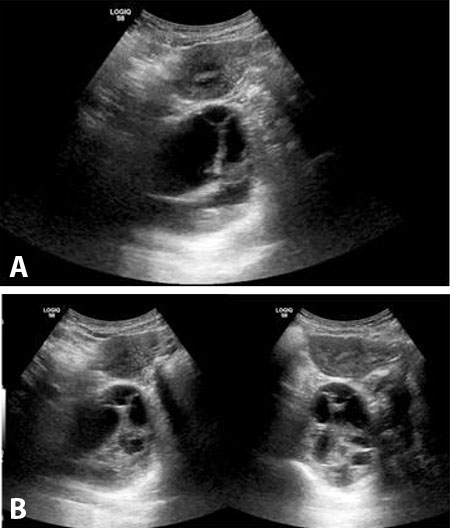

The first ultrasound examination revealed anhydramnios. The kidneys appeared normal and well-differentiated, the bladder was not visualized, and the stomach appeared small. On the same day, a cordocentesis was performed, showing elevated β2-microglobulin (6.91 mg/L), normal cystatin C (0.62 mg/L), and a normal molecular karyotype.

At 33 weeks and 3 days of gestation, severe pulmonary and renal hypoplasia were noted. At 36 weeks and 2 days, a small amniotic fluid pocket became visible for the first time, along with clearly identifiable bladder and stomach structures. The kidneys remained well-differentiated and non-hypoplastic.